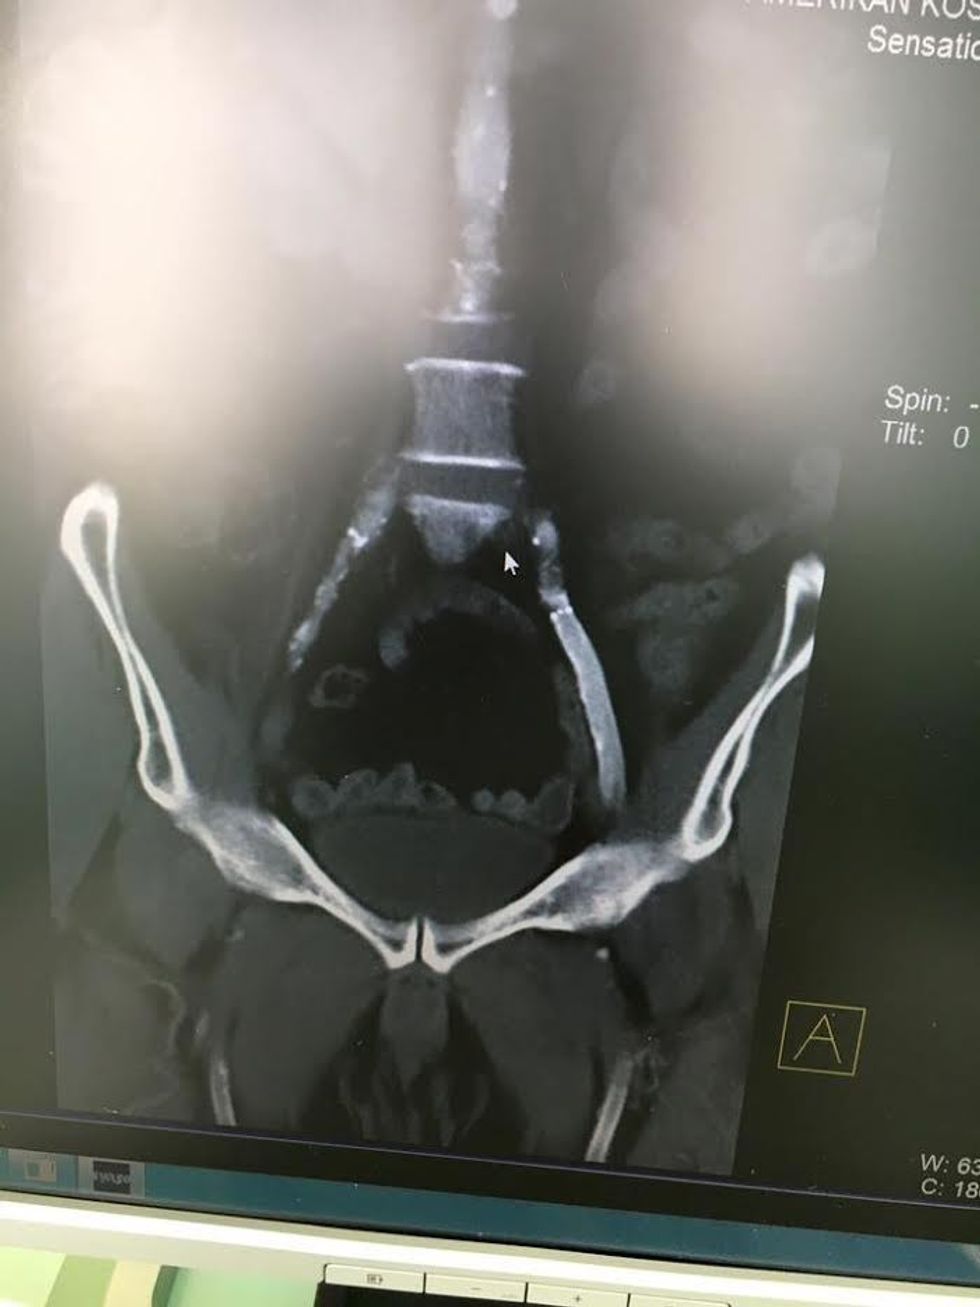

Pacientit i është bërë hapja e stentit periferik të thrombozuar (mbyllur) në gjithë aksin e arterieve të ekstremitetit (këmbës), pa i dëmtuar stentet, procedurë e cila është realizuar me sukses në Spitalin Amerikan nga Dr. Elmi Olluri – Kirurg Vaskular, me ndihmën e ekipit asistues në sallë.

Këto stente pacientit i janë vendosur në SHBA para disa viteve. Një procedurë e tillë e realizuar në kohë urgjente dhe me profesionalizëm, rezultoi me shpëtimin e këmbës nga amputimi, amputim i cili në qendrat e rajonit do të ndodhte thuajse 100 për qind. Por, falë profesionalizmit dhe përvojës arrihet që edhe stentet të hapen me sukses.